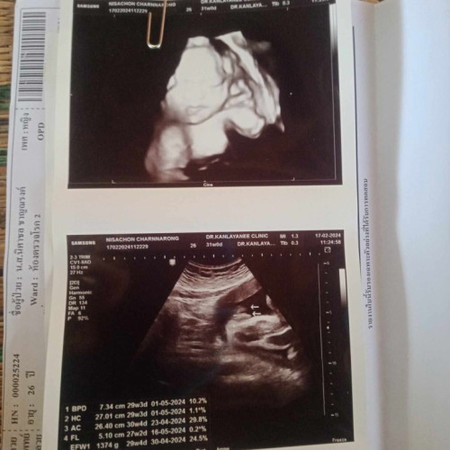

29+4น้ำหนัก1374 หมอบอกตำกว่าเกณฑ์นิด1 เเนะนำเเนวบำรุงหน่อยจ้า